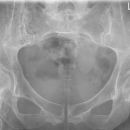

ISG p.-a.

Technik

• FDA: 100 cm

• Ausgangsformat: 24/30 quer

• mit Raster

• Röhrenkippung 10 ° cranio-caudal

Lagerung

Bauchlage, Beine gestreckt

Zentralstrahl

Längsstrahl: Medianebene

Einblendung

oberes Licht 1 QF über Beckenkamm,

seitlich ca. 20 cm

Anmerkung

FDA ist 1,00 m, damit gehen auf Grund der Divergenz die Strahlen senkrecht durch die Fugen. Bei bauchigen Patienten etwas, am besten einen 45° Keil, unter das Becken legen, damit die ISG parallel zum Film stehen.

Qualitätskriterien

Symmetrische Darstellung des ventralen und des dorsalen unteren Anteils der Iliosakralgelenke